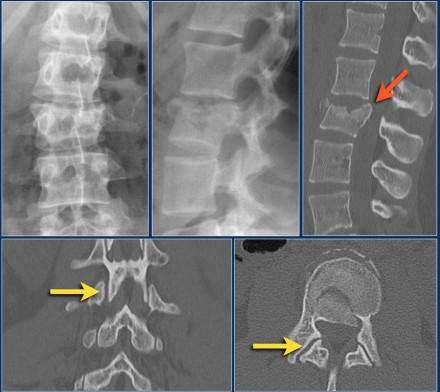

Case 3

Look at the images.

How would you describe the morphology and the PLC?

The findings are:

- Morphology: Translation - 3 points

- PLC: always disrupted in translation - 3 points

- TLICS: 6 points